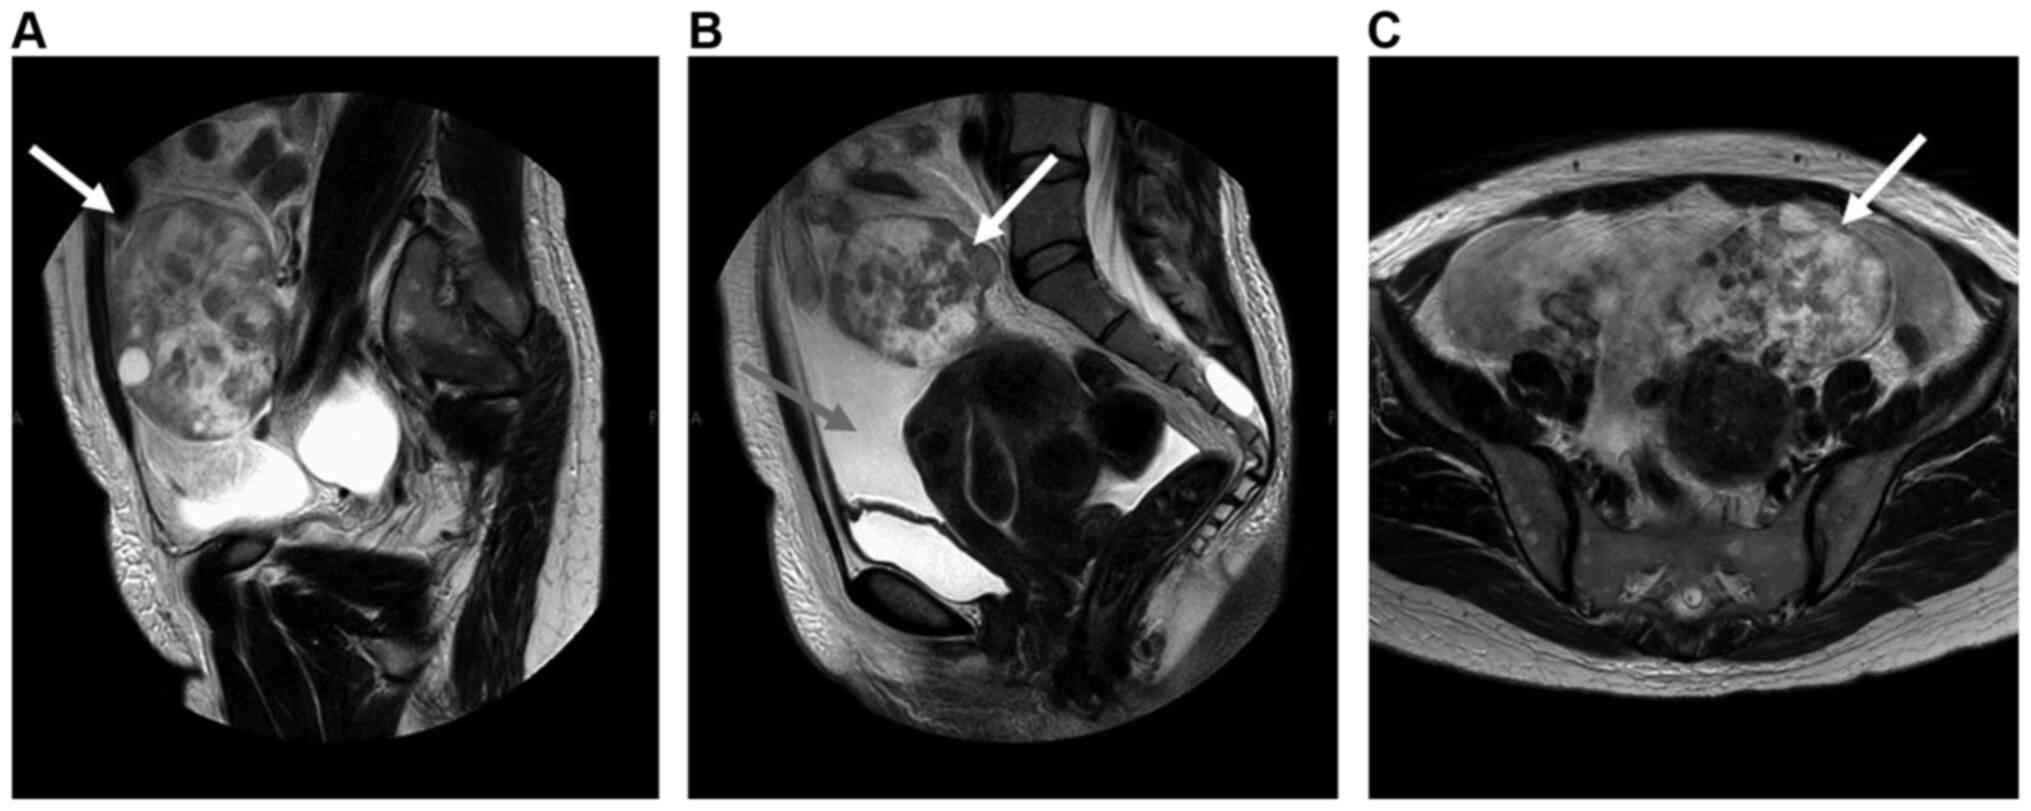

Ovarian metastasis from breast cancer mimicking a primary ovarian neoplasm: A case report

Ovarian metastasis (OM) from breast cancer accounts for 3‑38% of all ovarian neoplasms and is associated with various characteristic clinical presentations, such as pseudo‑Meigs syndrome and Krukenberg tumor. Accurate diagnosis of OM may be challenging, as such lesions are frequently asymptomatic until they reach a large size. Occasionally, metastatic ovarian cancer is detected prior to the diagnosis of the primary tumor. Immunohistochemistry plays an important role in distinguishing primary ovarian tumors from extraovarian tumor metastases and may be helpful for identifying the primary tumor site. We herein report a case of OM from breast cancer masquerading as primary ovarian cancer. However, the correct diagnosis was made based on histopathological and immunohistochemical examinations. The patient had bilateral breast cancer, namely invasive lobular carcinoma of the left breast and ductal carcinoma of the right breast. Due to the presence of bilateral synchronous breast tumors, the possibility that the patient had hereditary breast and ovarian cancer syndrome or other relevant genetic factors was considered. Immunohistochemistry plays a key role in distinguishing between primary ovarian tumors and OM, and it was also important for confirming the metastatic nature of the ovarian lesion and diagnosing the primary tumor in the present study.

Figure 1